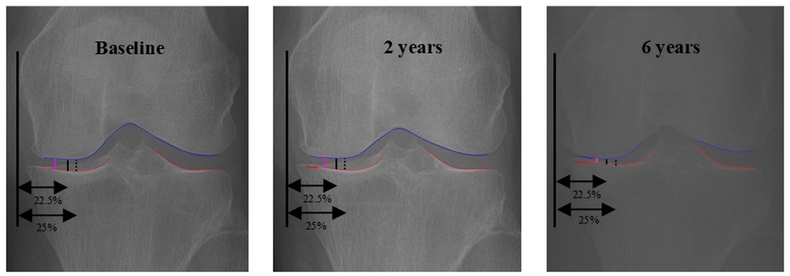

무릎 골관절염의 중증도는 보통 X-ray에서 허벅지뼈(대퇴골)와 정강이뼈(경골) 사이의 간격(JSW)을 측정해 평가한다. 기존에는 관절의 특정 위치(JSW225, JSW250)를 고정해 간격을 쟀으나, 이는 환자마다 다른 해부학적 특성과 비대칭적인 마모 상태를 충분히 반영하지 못해 실제 마모가 심한 부위를 놓칠 위험이 있었다. 반면 이번에 개발된 oJSW는 AI가 관절 내부를 자동으로 탐색해 가장 좁은 지점을 수직으로 측정하므로 개인별 마모 상태를 정밀하게 반영한다.

연구팀은 미국 국립보건원(NIH)의 대규모 코호트(OAI) 자료를 활용해 참여자 3,855명의 무릎 영상 15,313개를 최대 72개월(6년)간 추적 분석했다. 이는 딥러닝 기반의 신규 영상 지표를 대규모 종적 코호트(시간에 따른 동일 집단 추적)에서 기존 표준 지표들과 비교 검증한 최초의 연구다.